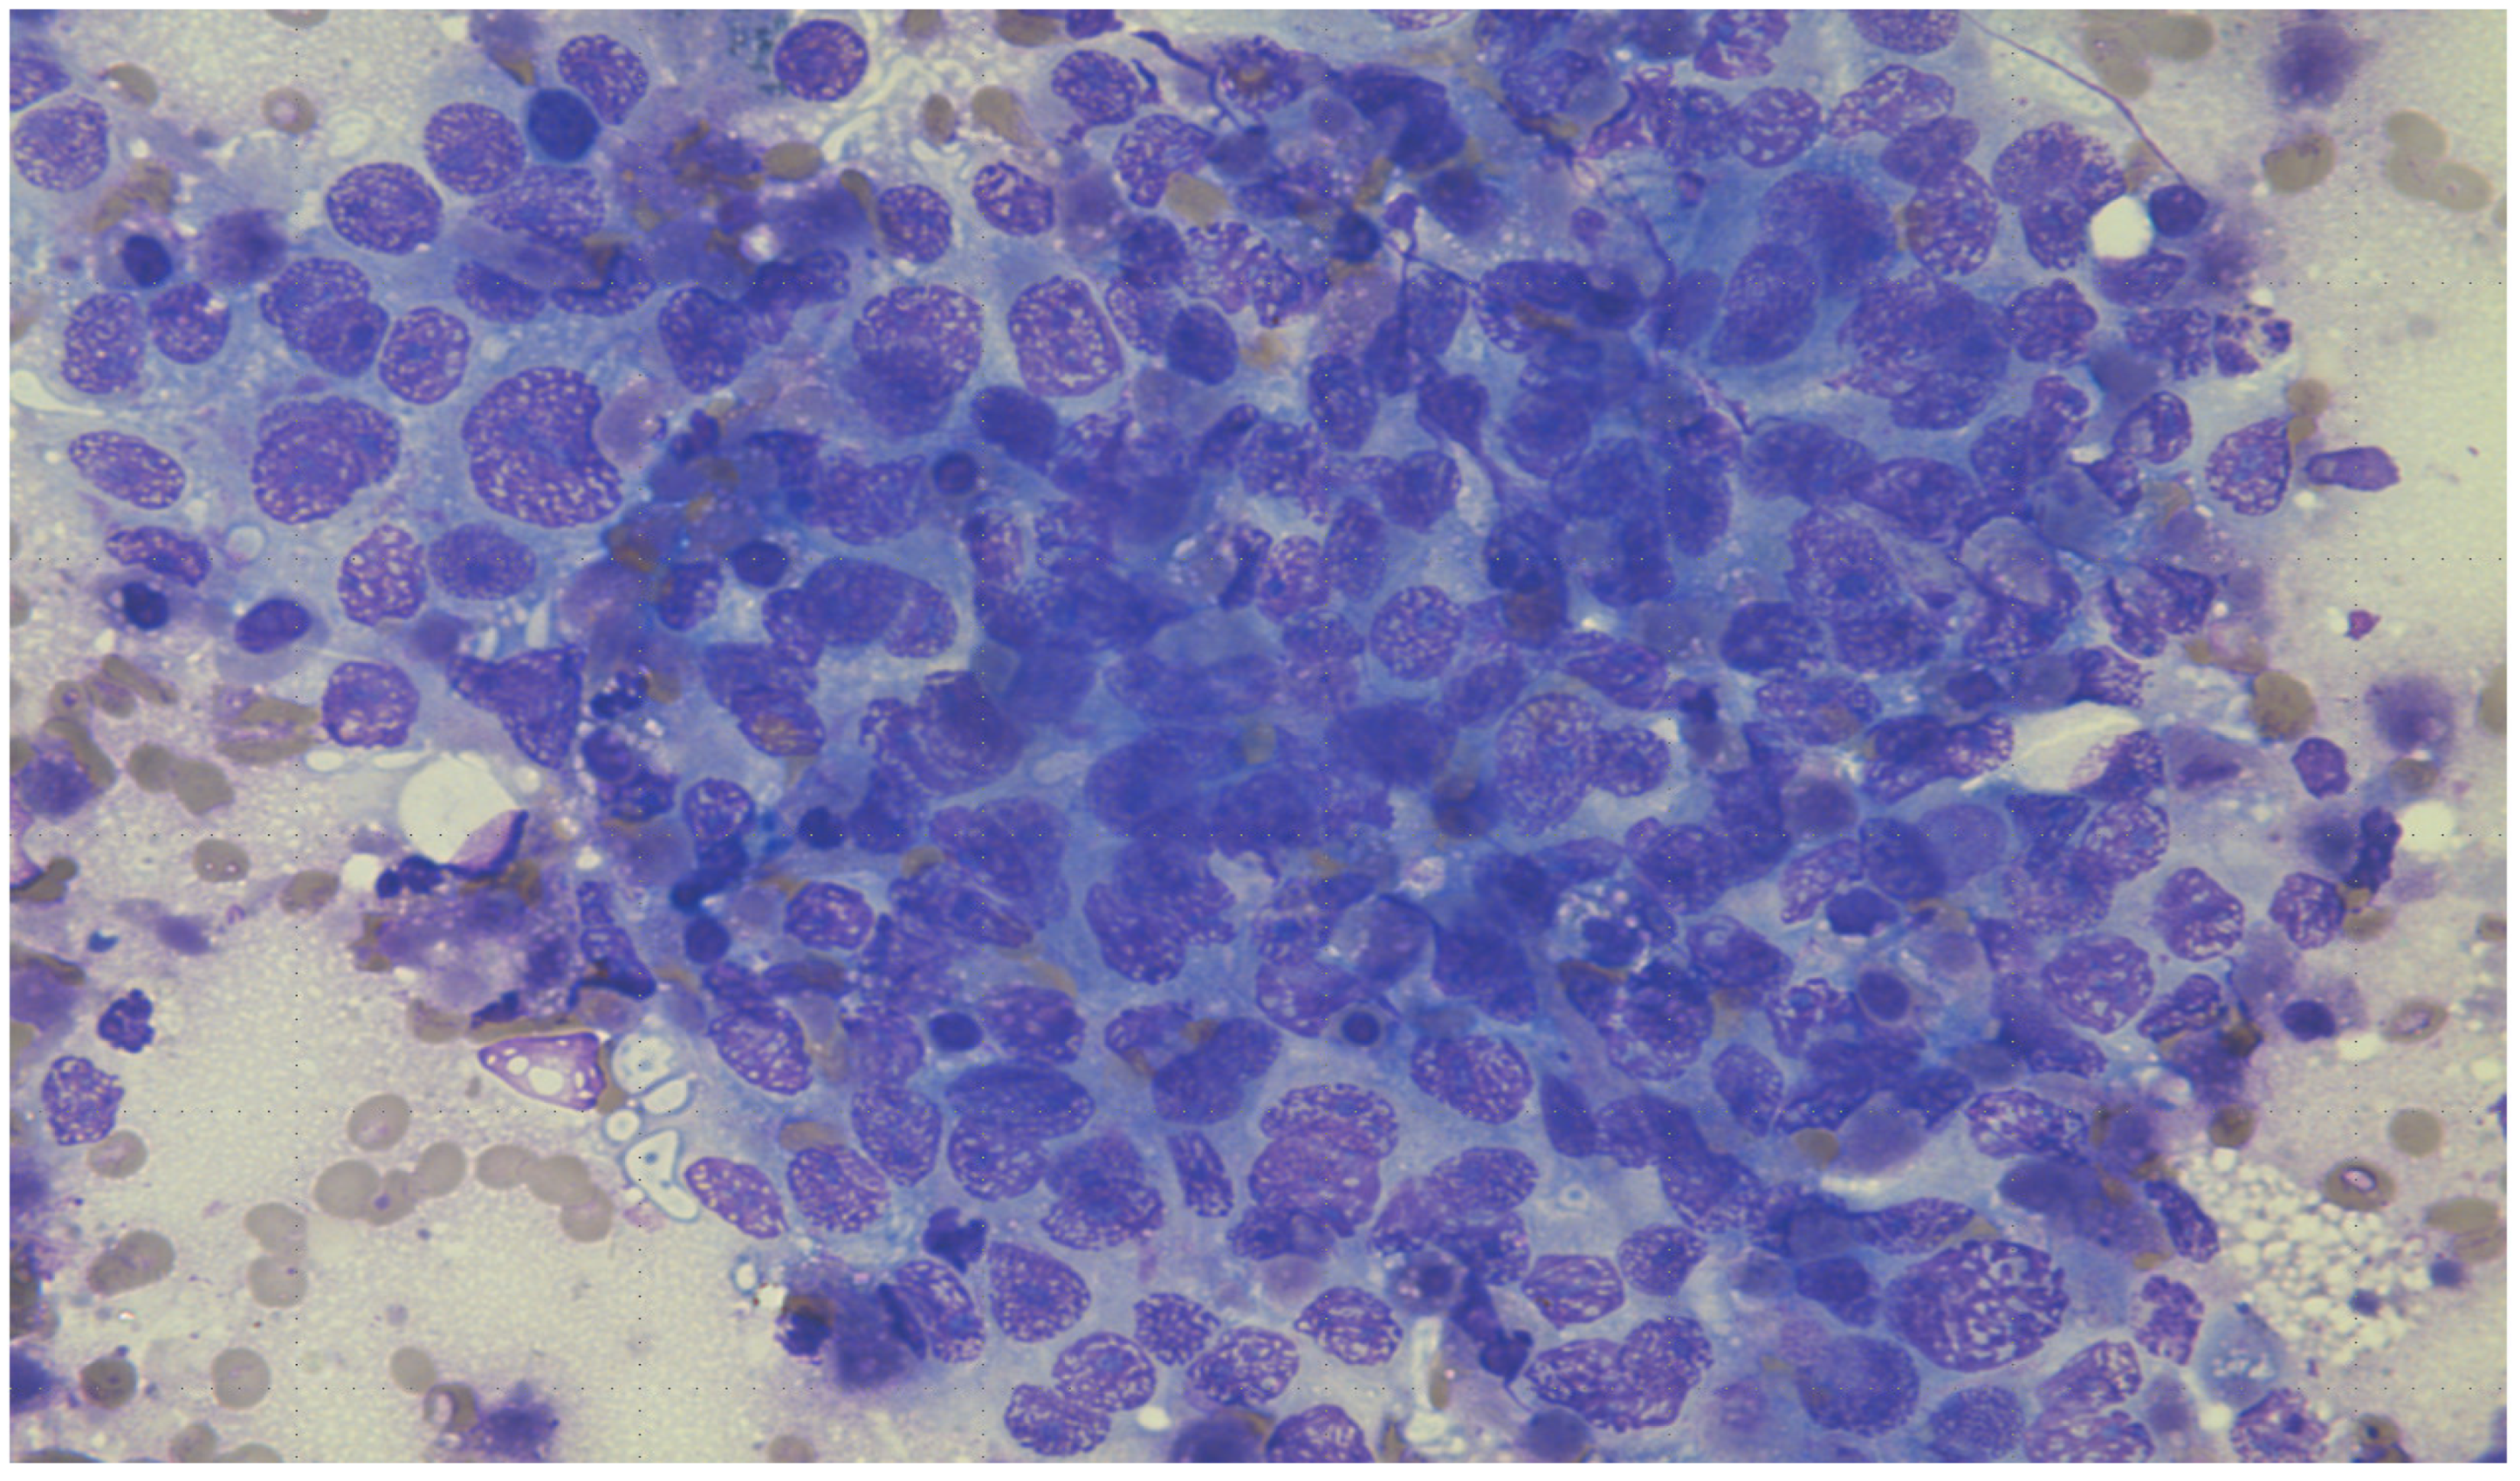

The clinical team decided to perform an ultrasound-guided fine-needle aspiration and biopsy of one of the liver lesions. Touch preparation (Figure 4: DiffQuick, 200X power field) and the biopsy (Figure 5: H&E, 100X power field) showed sheets of malignant epithelioid cells with a high nuclear-to-cytoplasmic ratio, vacuolated eosinophilic cytoplasm, areas of necrosis (Figure 6: H&E, 400X power field), and up to five mitoses per one high-power field (Figure 7: H&E, 400X power field).

Figure 4.

DiffQuick, 200X. The touch preparation of the ultrasound-guided fine-needle aspiration and biopsy of one of the liver lesions showing sheets of malignant epithelioid cells with a high nuclear-to-cytoplasmic ratio.